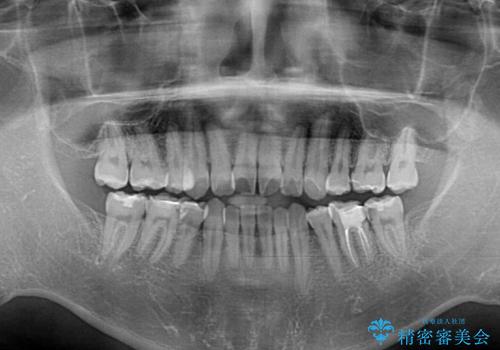

- 高校時代に行った抜歯矯正が後戻りをしたとのことで来院された患者様です。

下顎骨が左側に変位しているため、正中が合わないことは予想できましたが、歯列が整った後も咬み合わせが安定せず、咬み合わせを落ち着かせるために1年以上の期間を要しました。